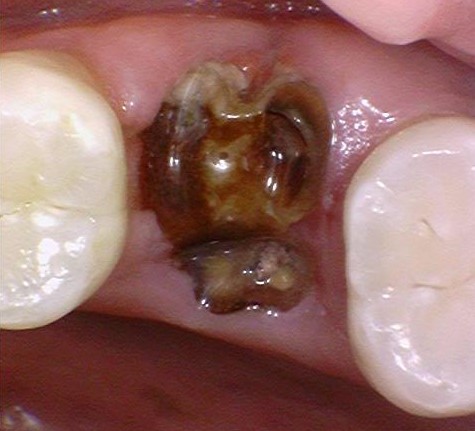

![[서울시청역치과] 20대, 30대도 임플란트를 하나요?? +네비게이션임플란트안내 관련 이미지 2](https://pub-9f2bb3498faf4d1d8714b41df24753e3.r2.dev/content/clinics/archive/rseeanjxfu/naver_blog/yonseiyegam/assets/by_hash/24ff349f6aa302f2f7c4ceeed8a13a12f1e60db20f221171d0f34fa1d83b9029.jpg)

제때 임플란트를 하지 않아 위의 치아가 아래로 내려와서

아래 치아를 회복하려면 위의 치아를 교정하거나 깎아서 크라운을 해야하는 상황입니다.